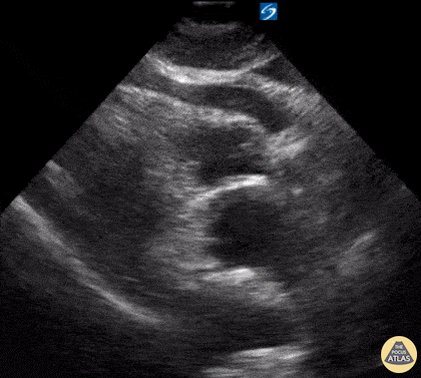

13 - Normal kidney